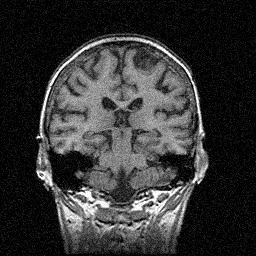

磁気共鳴画像(MRIで得られた画像)

雑音を付加した画像に対し,雑音処理を実施

雑音画像(SNR: 26.0 dB) FREBAS雑音除去像(SNR:

29.2 dB)